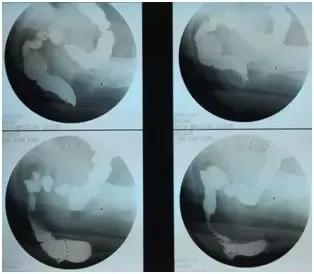

1.排粪造影:是诊断直肠前突的可靠影像学依据。可显示 排便时直肠前下壁向前突出,并可测量直肠前突的深度和宽度,判断直肠排空障碍的程度。如合并耻骨直肠肌综合征,则呈现典型的“鹅颈征”。合并粘膜脱垂时可见:“杯口征”。